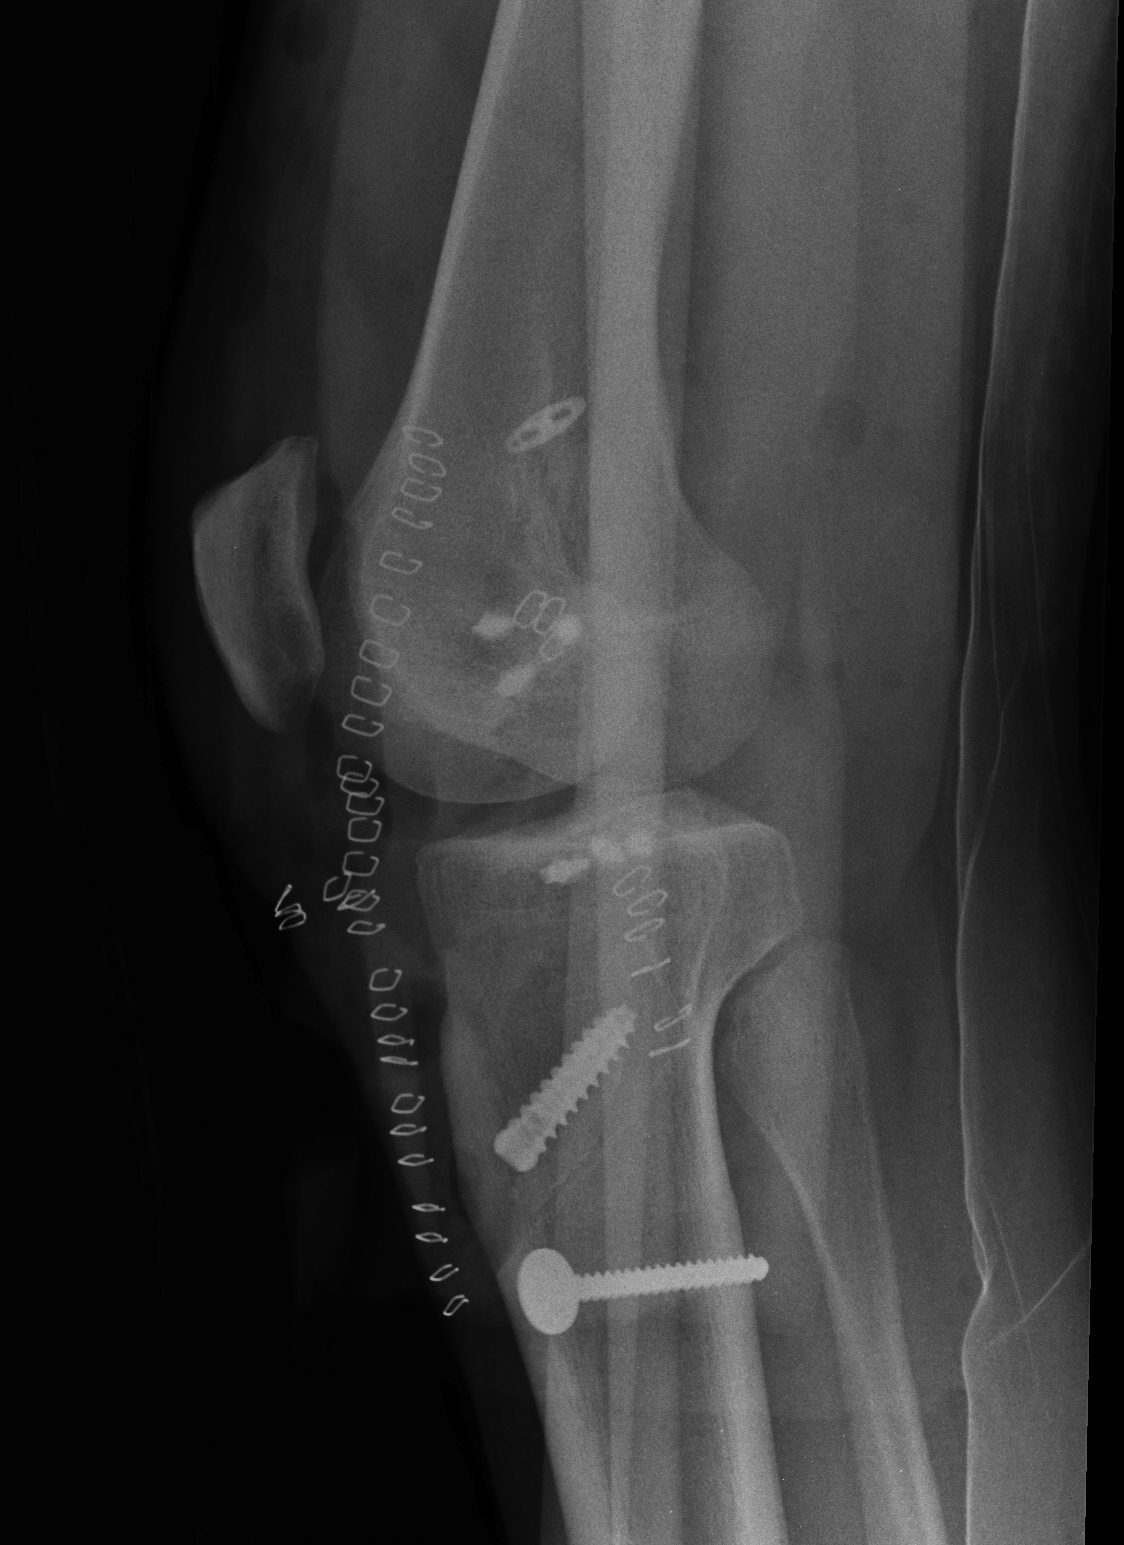

After 6 – 12 weeks, consideration of surgery can begin. An xray of both legs is important, to ensure that there is normal leg alignment. As a general rule, the ACL is reconstructed with the patella or hamstring tendon, and any significant PCL injuries reconstructed with tendoachilles allograft. Open surgery using tendoachilles allograft is required to reconstruct the LCL, on the outside of the knee.